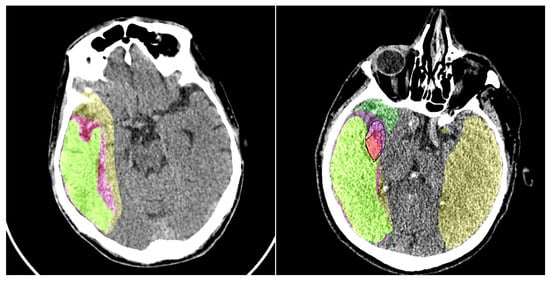

This study primarily focuses on enhancing the performance of multiclass segmentation in brain CT images. The input image is segmented into three regions: ischemic core, penumbra area, and background. The segmentation model produces three output masks, each corresponding to a specific region, with the label “1” representing a significant region and “0” otherwise (Figure 1).

The dataset contains anonymous CT scan results from 112 patients who were hospitalized during the acute phase of ultra-early ischemic stroke within 24 h of the onset of the first symptoms. It includes three classes of labeled regions: ischemic core, penumbra, and background. The images were annotated by an experienced radiologist, who outlined the penumbra and core regions on each relevant slice. In total, the dataset includes 10,165 images, with 8376 slices used as the training set, 980 images reserved for validation (hyperparameter tuning), and 809 slices used for testing. Each image in the dataset has a resolution of 512 × 512 pixels. An example of images from the dataset is shown in Figure 5.